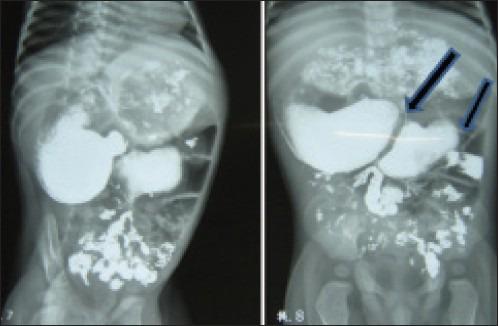

Congenital double duodenal diaphragms in an infant.

Duodenal stenosis usually occurs in isolation and has a variable presentation in infancy due to partial obstruction. An unusual case of congenital double duodenal diaphragms in an infant presenting as failure to thrive has been described and pertinent literature has been reviewed herein. Excision of webs with double Heineke-Mikulicz closure was performed.